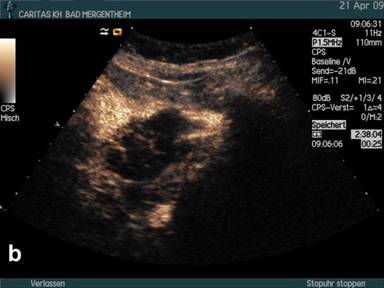

Figure 1. B-mode imaging (a.) and contrast enhanced ultrasound (CEUS) (b.) in a patient with histologically proven pseudocyst of the pancreas. Small peripherally nodular structures are delineated (arrow) analysing the arterial phase (b.) indicating neoplasia. Surgery and consecutive histology revealed pseudocyst and no neoplasia. |

Using conventional B-mode mostly peripherally located solid nodules (with or without septae formation) were displayed in 36/64 (56.3%) patients implying neoplastic disease. The results are shown in Table 2. In 2/36 (5%) of these patients with nodules at the edge of the cyst and the final diagnosis of pseudocyst contrast enhancement was found in the peripherally located solid nodules (Figure 1) which was the reason for the 2 false positive findings using CEUS in histologically/cytologically proven pseudocysts. The pseudocyst transversing arterial macrovessels could only be identified using CEUS and conventional ultrasound in combination in 13/35 (37.1%) patients.